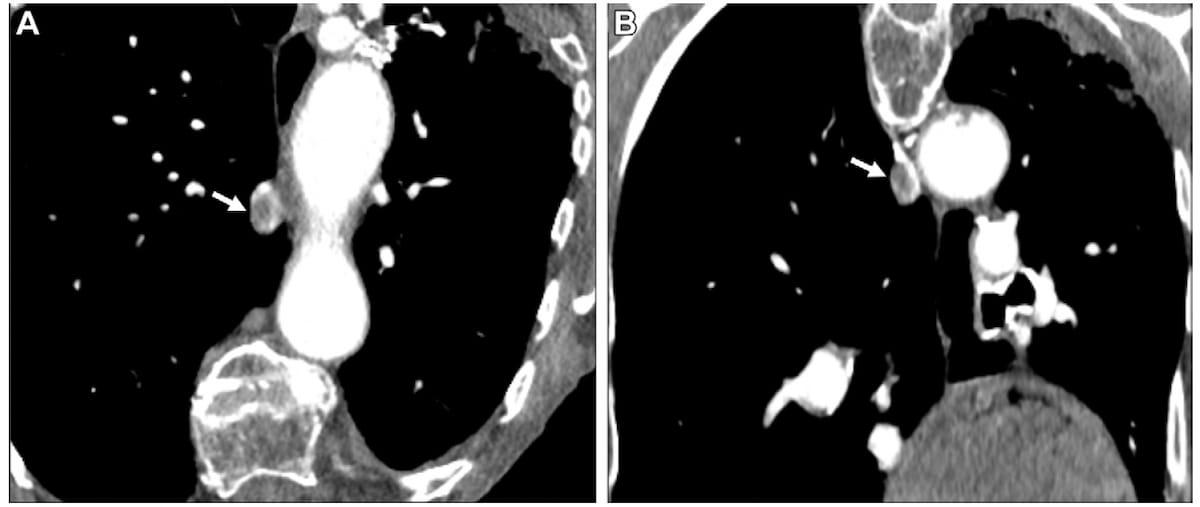

The Pulmonary Embolism (PE) Triage and Notification (PETN) module with RapidAI’s RapidPE platform reportedly demonstrated over 90 percent sensitivity and specificity rates for detection of central PE on computed tomography (CT), according to multicenter study findings presented at the 9th Annual Pulmonary Embolism Symposium.